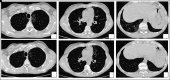

Clinical case: We report the case of a patient affected by autoimmune PAP who developed pleuro-parenchymal fibroelastosis (PPFE) after 6 years of disease and underwent bilateral lung transplantation due to end stage respiratory failure.